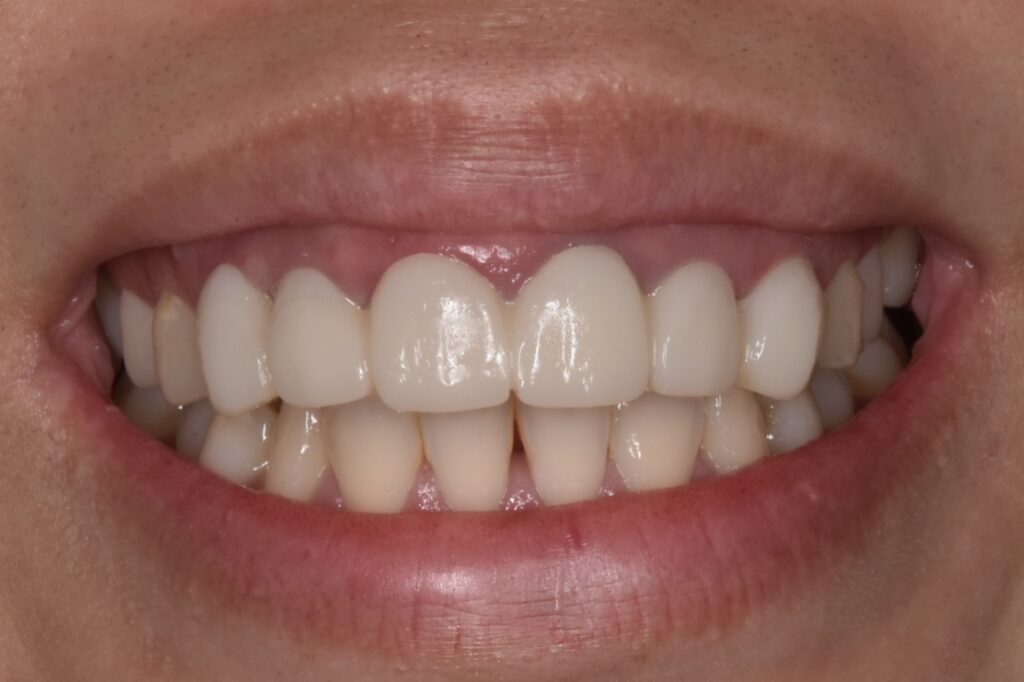

神経治療から土台の立て直しそして仮歯へ

前歯の歯ぐきの高さがチグハグだったため、歯肉整形をさせて頂きました。歯ぐきの位置を整え綺麗に見えるようにしています。

仮歯は歯の位置が変わらないように連結で製作しています。